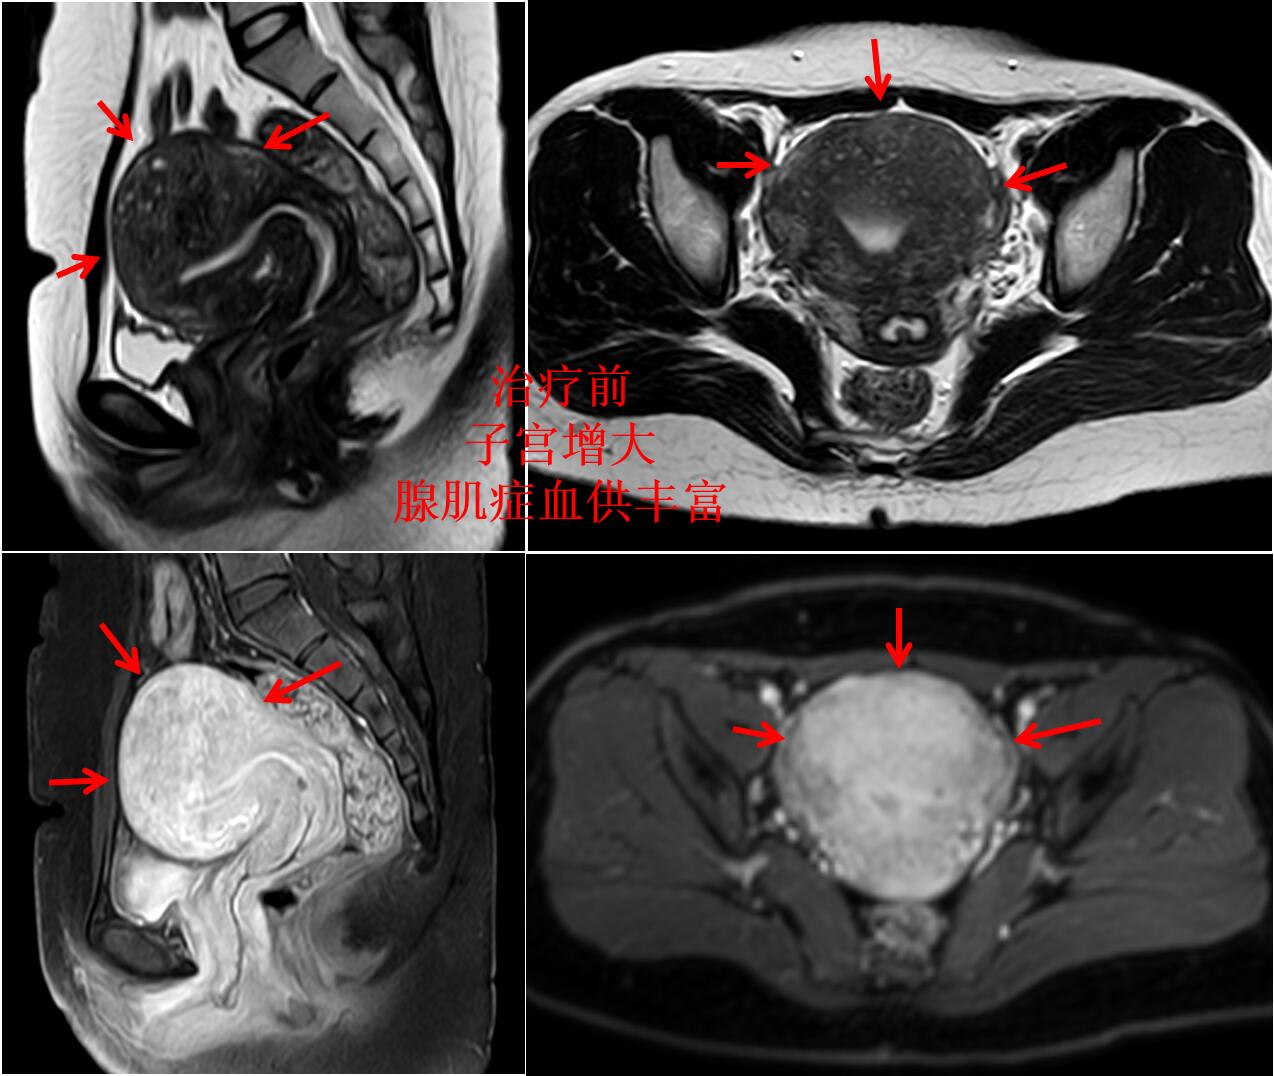

门诊磁共振检查:子宫明显增大(10.8*9.2*8.7cm3),子宫腺肌症,以宫底及后壁明显(如下图)。

介入微创消融治疗后无明显痛经,3个月后复查磁共振显示:子宫腺肌病病灶灭亡,子宫缩小(如下图)。

介入微创消融治疗后1年痛经没法复发,复查磁共振显示:子宫大小恢复正常,腺肌症灭亡吸收排出(如下图)。